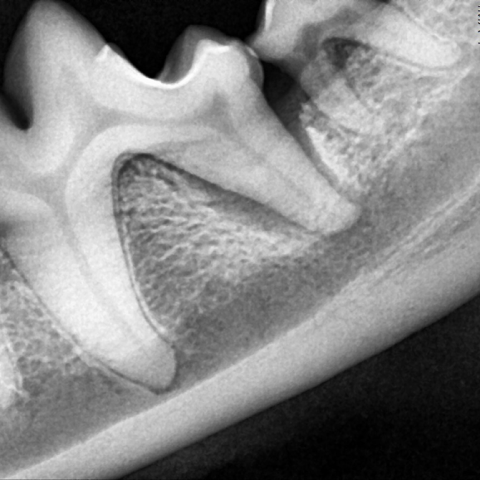

스케일링 전

스케일링 후

수술 전

수술 후